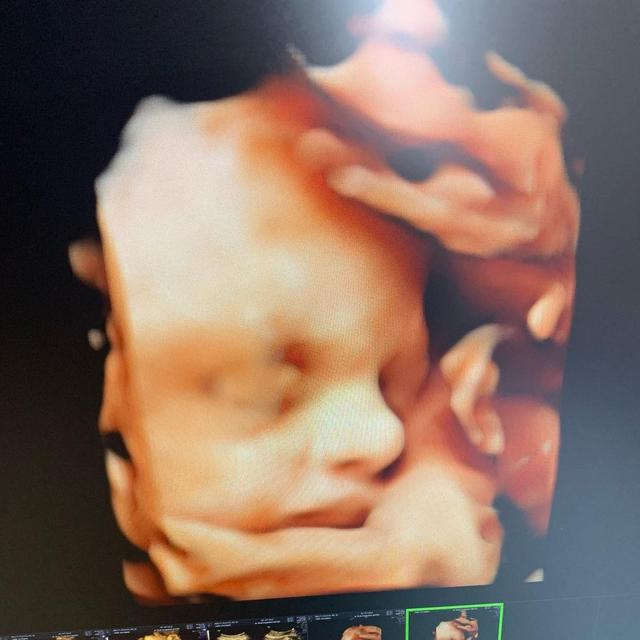

7. Ini dia potret hasil foto USG janin yang dikandung Nella Kharisma

5. Usai periksa kandungan, ia pun nampak sangat bahagia bisa melihat sosok janin yang ada di kandungannya

Momen periksa kandungan tentu menjadi momen yang membahagiakan. Dimana saat seorang calon ibu hamil, sangat menantikan kabar dari calon buah hatinya setiap bulan. Begitu pula dengan Nella Kharisma yang terlihat sangat bahagia saat ia melihat foto USG dari janinnya.